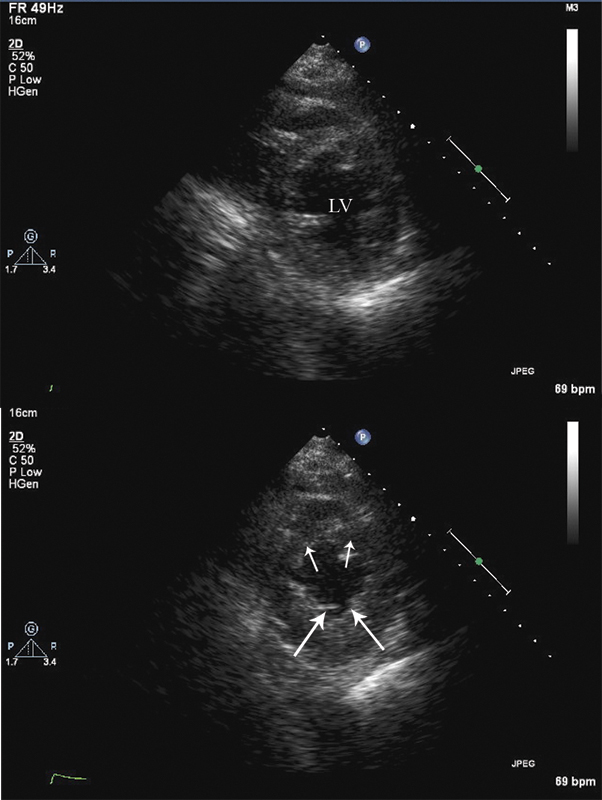

فحوصات تشخيصية لبعض امراض القلب والشرايين التاجية